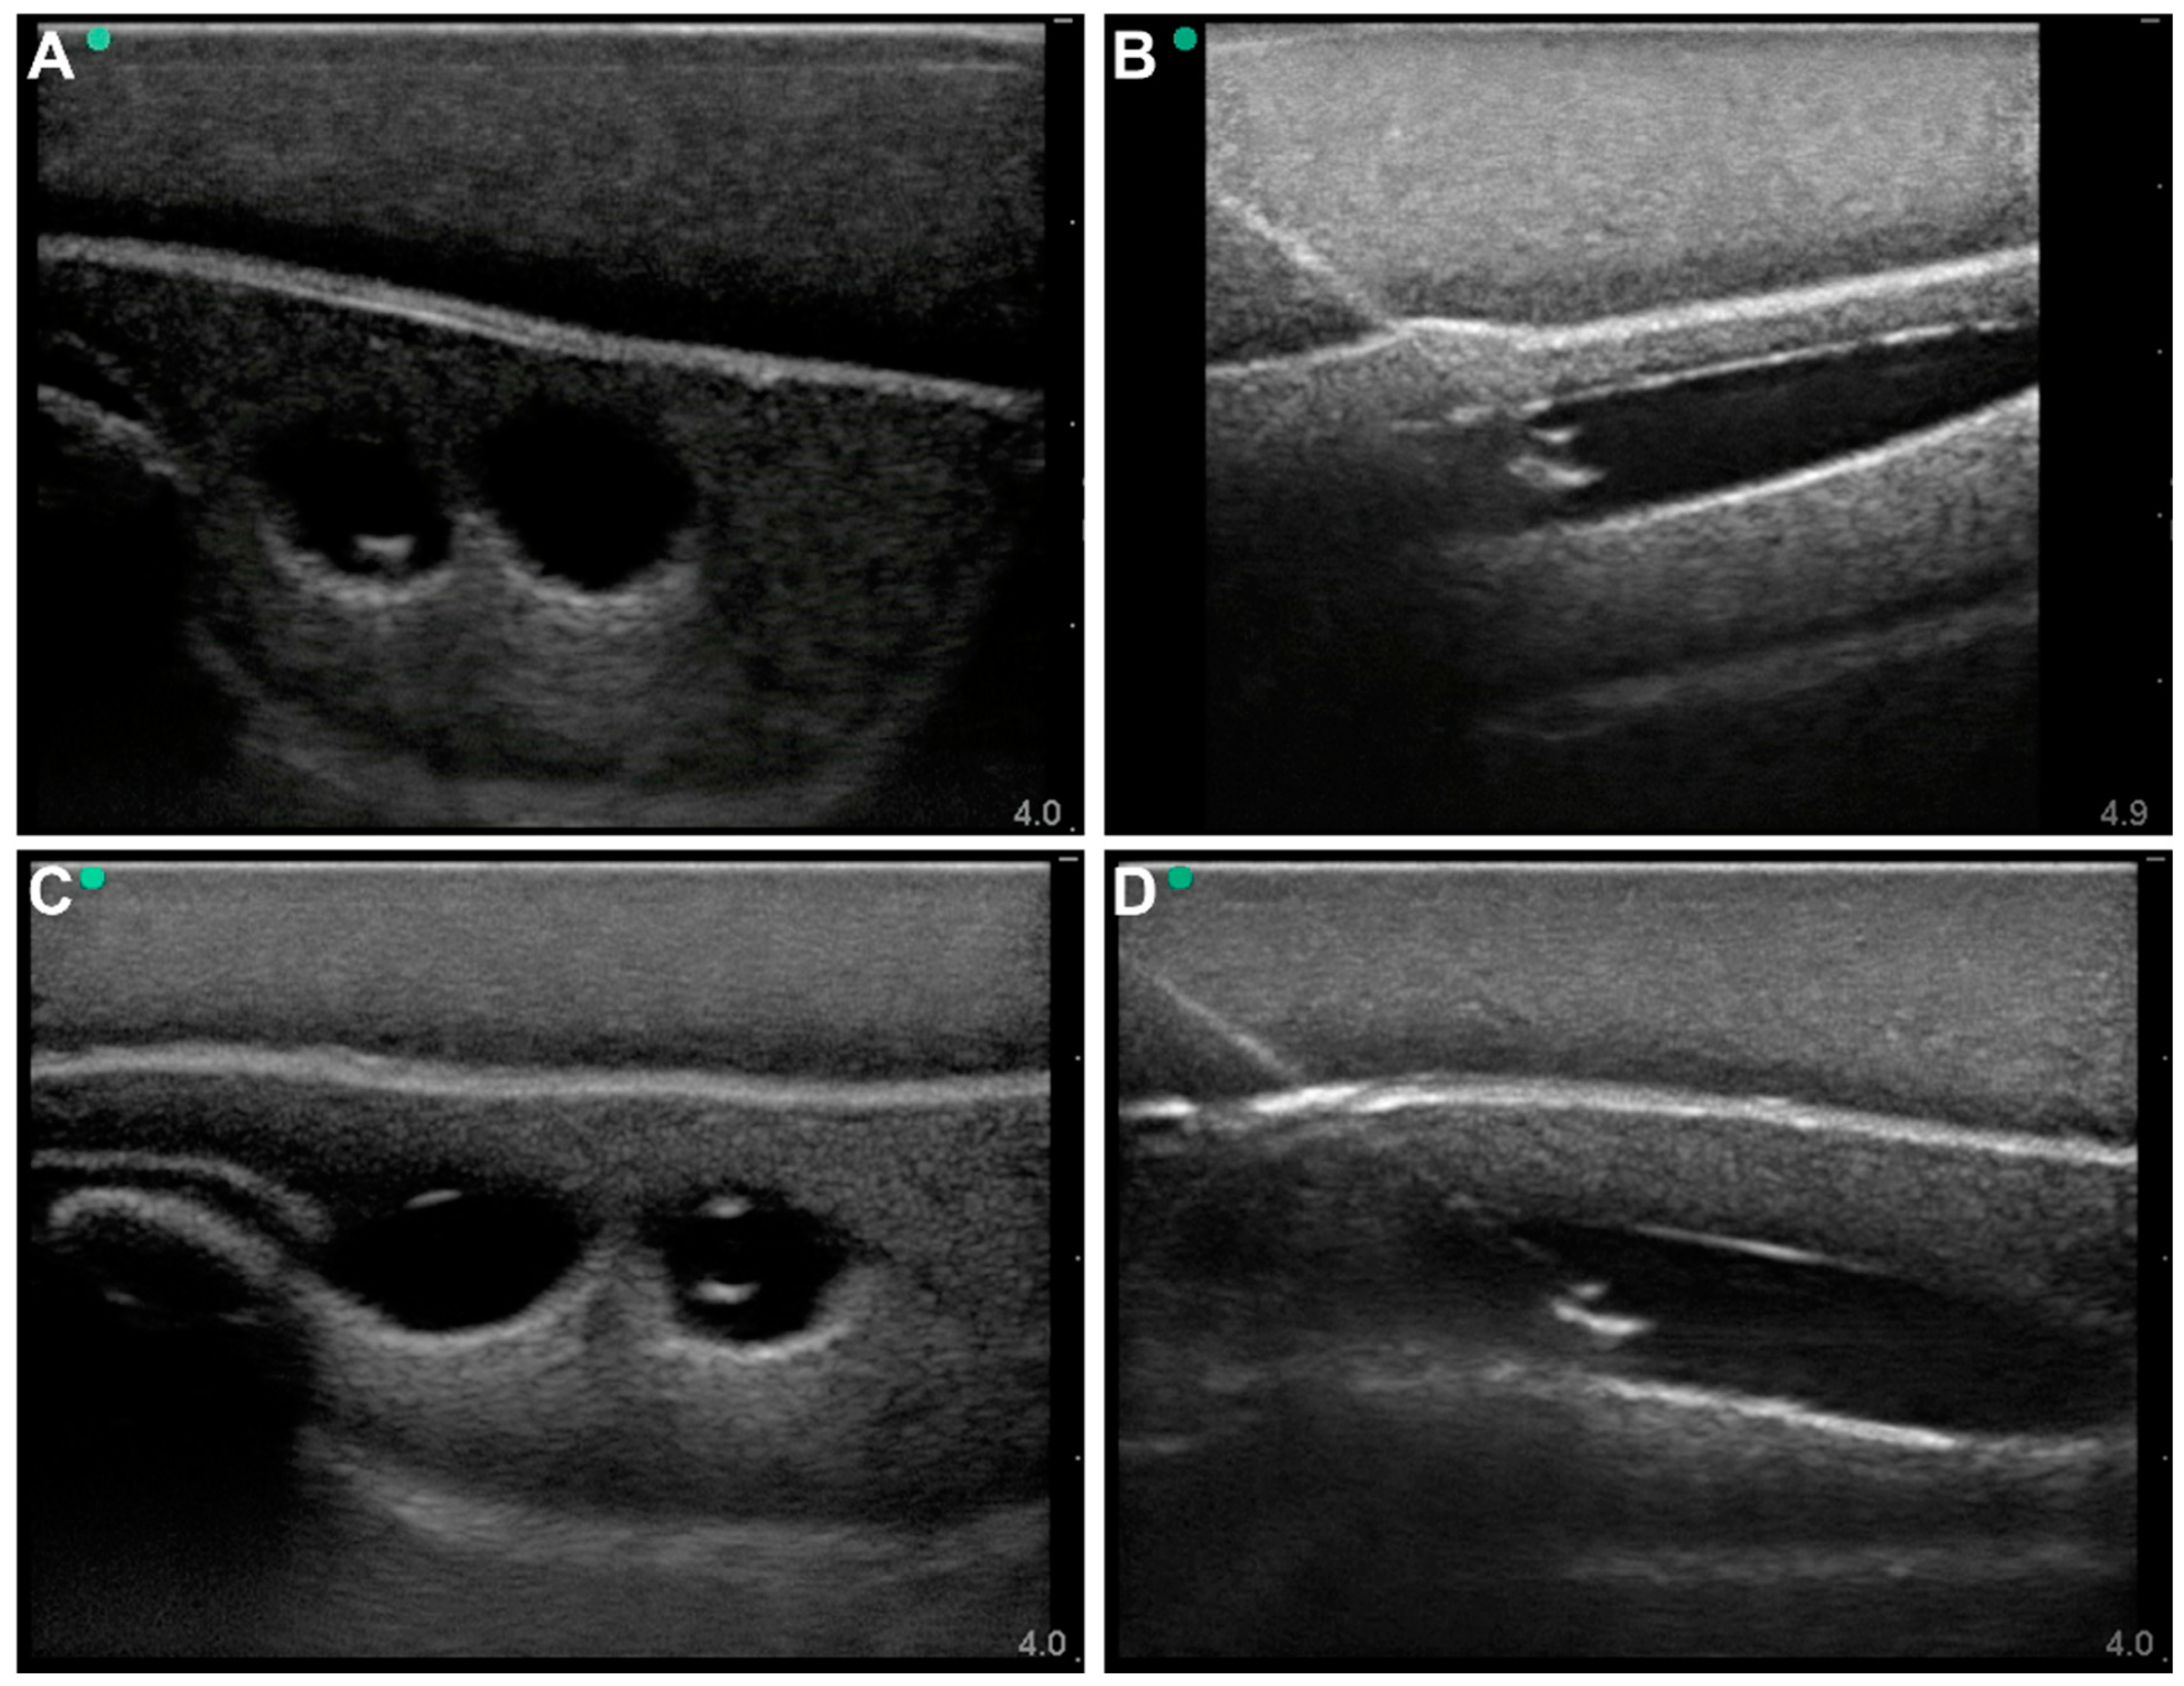

2.2. Commercially Available Ultrasound Trainers

2.3. Lower-Body Ex Vivo Porcine Model

3.1. Commercial Test Results

3.2. Lower-Body Ex Vivo Porcine Model Results